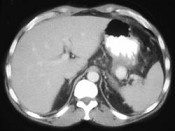

- 单项选择题男,36岁, 反复剑突下胀痛5年,加重伴间断性呕血、黑便3年, 有6年慢性胰腺炎病史,CT检查如图, 最可能的诊断是  (    )

- A、脾血管瘤伴慢性胰腺炎

- B、脾动脉瘤伴慢性胰腺炎

- C、脾假性动脉瘤伴慢性胰腺炎

- D、胰腺转移瘤伴慢性胰腺炎

- E、胰腺癌伴慢性胰腺炎